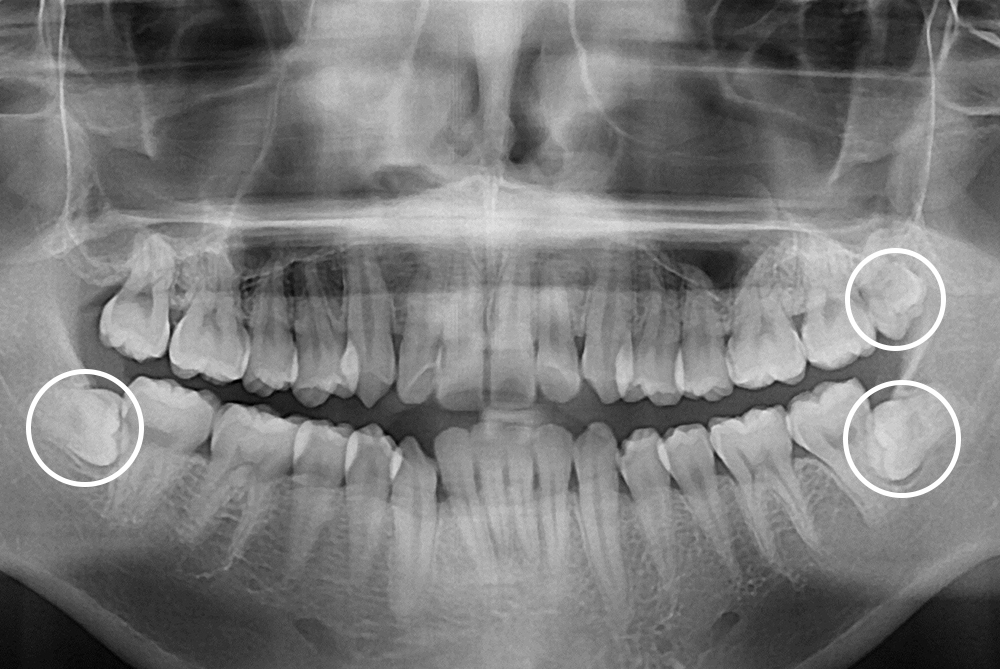

[사랑니] 매복 사랑니 발치

치료후 : 2019-04-15

세종치과는 구강악안면외과학 박사이신 원장님이 발치하는 치과입니다.